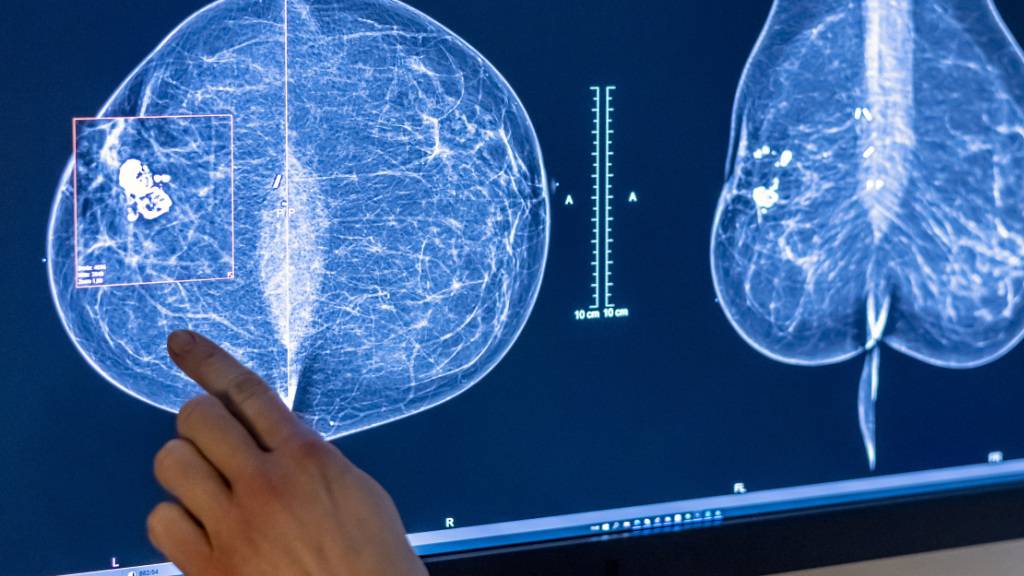

Viele Krebsfälle gehen auf vermeidbare Ursachen zurück. (Archivbild)

© KEYSTONE/DPA/HANNIBAL HANSCHKE